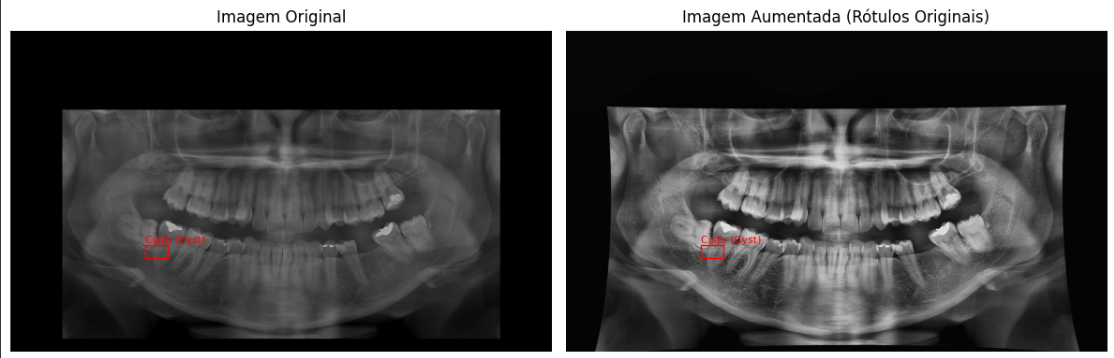

Aumentando a quantidade de dados

Como citado anteriormente, um problema grande era a falta de dados para que o modelo aprendesse melhor o que, de fato, era um cisto odontológico, para isso foram implementadas ações para aumentar os dados, aplicando transformações de brilho, rotação, etc. Dessa forma aumenta a diversidade de dados e melhora a predição do modelo.